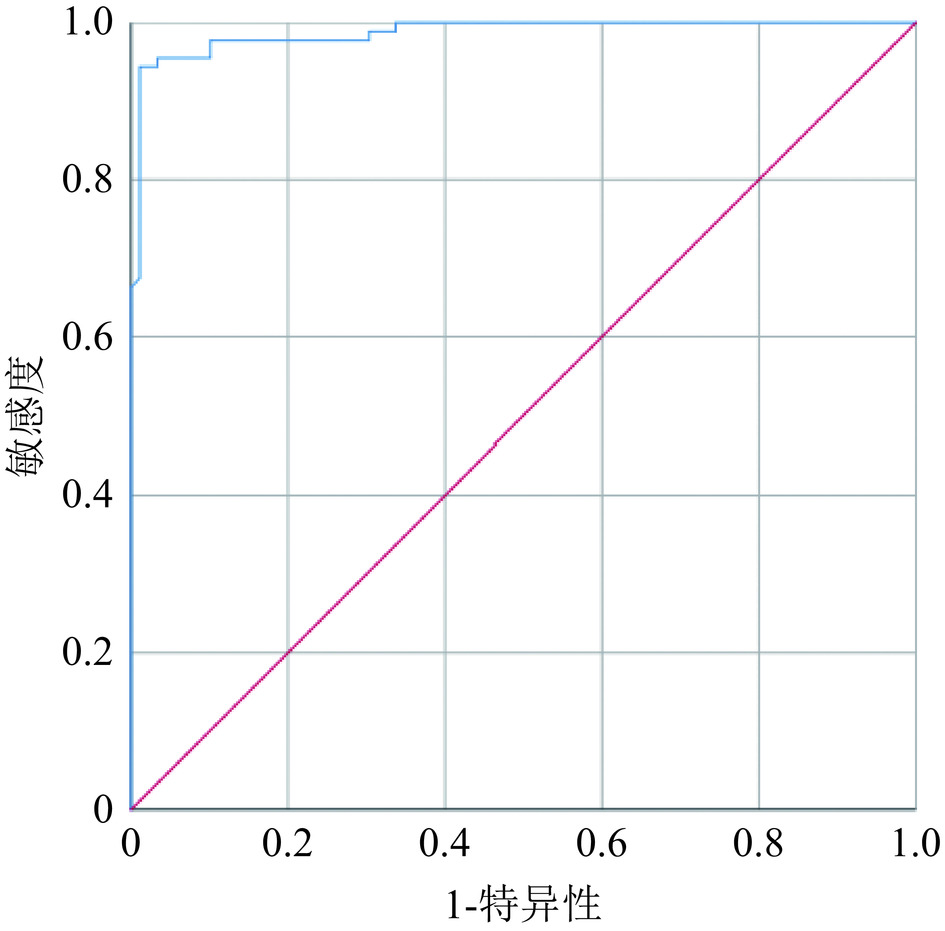

2.2 客观图像分析

以MRI为参考标准,总共有89个ⅡA期区域,D医生在VNCA图像上找出与T2 WI序列上相对应的骨髓水肿区域,测量得出89个异常CT值,对照组(在同一患者的同侧距骨上)测出89个正常骨髓区CT值。总共测出的178个CT值,经SPSS统计软件计算,病变区骨髓CT值(0.55±1.22)HU,对照组骨髓CT值(−48.30±1.24)HU(表3),病变区骨髓CT值与对照组CT值存在统计学差异(P<0.01)(图3)。病变区的CT值ROC曲线显示(图4),AUC值为0.987(95%置信区间:0.974−1.000),病变区骨髓CT值与对照组CT值的最佳截断值为−21.85 HU,此时的敏感性、特异性分别为92%和98.9%。

本研究结果尚显示,OLTⅡA期骨髓异常区与正常骨髓区CT值具有显著统计学差异,前者CT值明显高于后者,最佳截断值为−21.85 HU,其敏感性、特异性分别为92%和98.9%,与Foti等[37]研究结果(截断值为−20 HU,敏感性88%,特异性86.6%)相仿。表明CT定量检测对OLTⅡA期骨髓水肿的诊断具有重要的佐证意义。然而,由于设备、扫描参数、检测位点、受检者年龄等因素影响[38],有研究[37-38]显示最佳截断CT值存在较大差异,需要在实际工作中予以甄别。